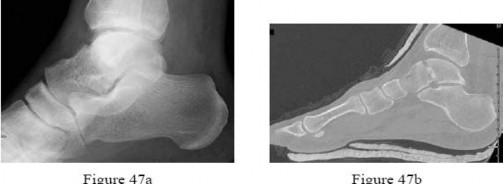

Question 29

A 32-year-old male falls from a ladder and sustains a Hawkins Type III fracture of the talar neck. By definition, a Hawkins Type III injury involves a talar neck fracture accompanied by which of the following patterns of dislocation?

Explanation

The Hawkins classification describes talar neck fractures: Type I is nondisplaced; Type II involves subtalar subluxation or dislocation; Type III involves dislocation of both the subtalar and tibiotalar (ankle) joints (the talar body extrudes posteromedially); Type IV (added by Canale) involves dislocation of the subtalar, tibiotalar, and talonavicular joints. The risk of avascular necrosis (AVN) increases substantially with each grade, approaching 100% in Type III/IV if not reduced urgently.